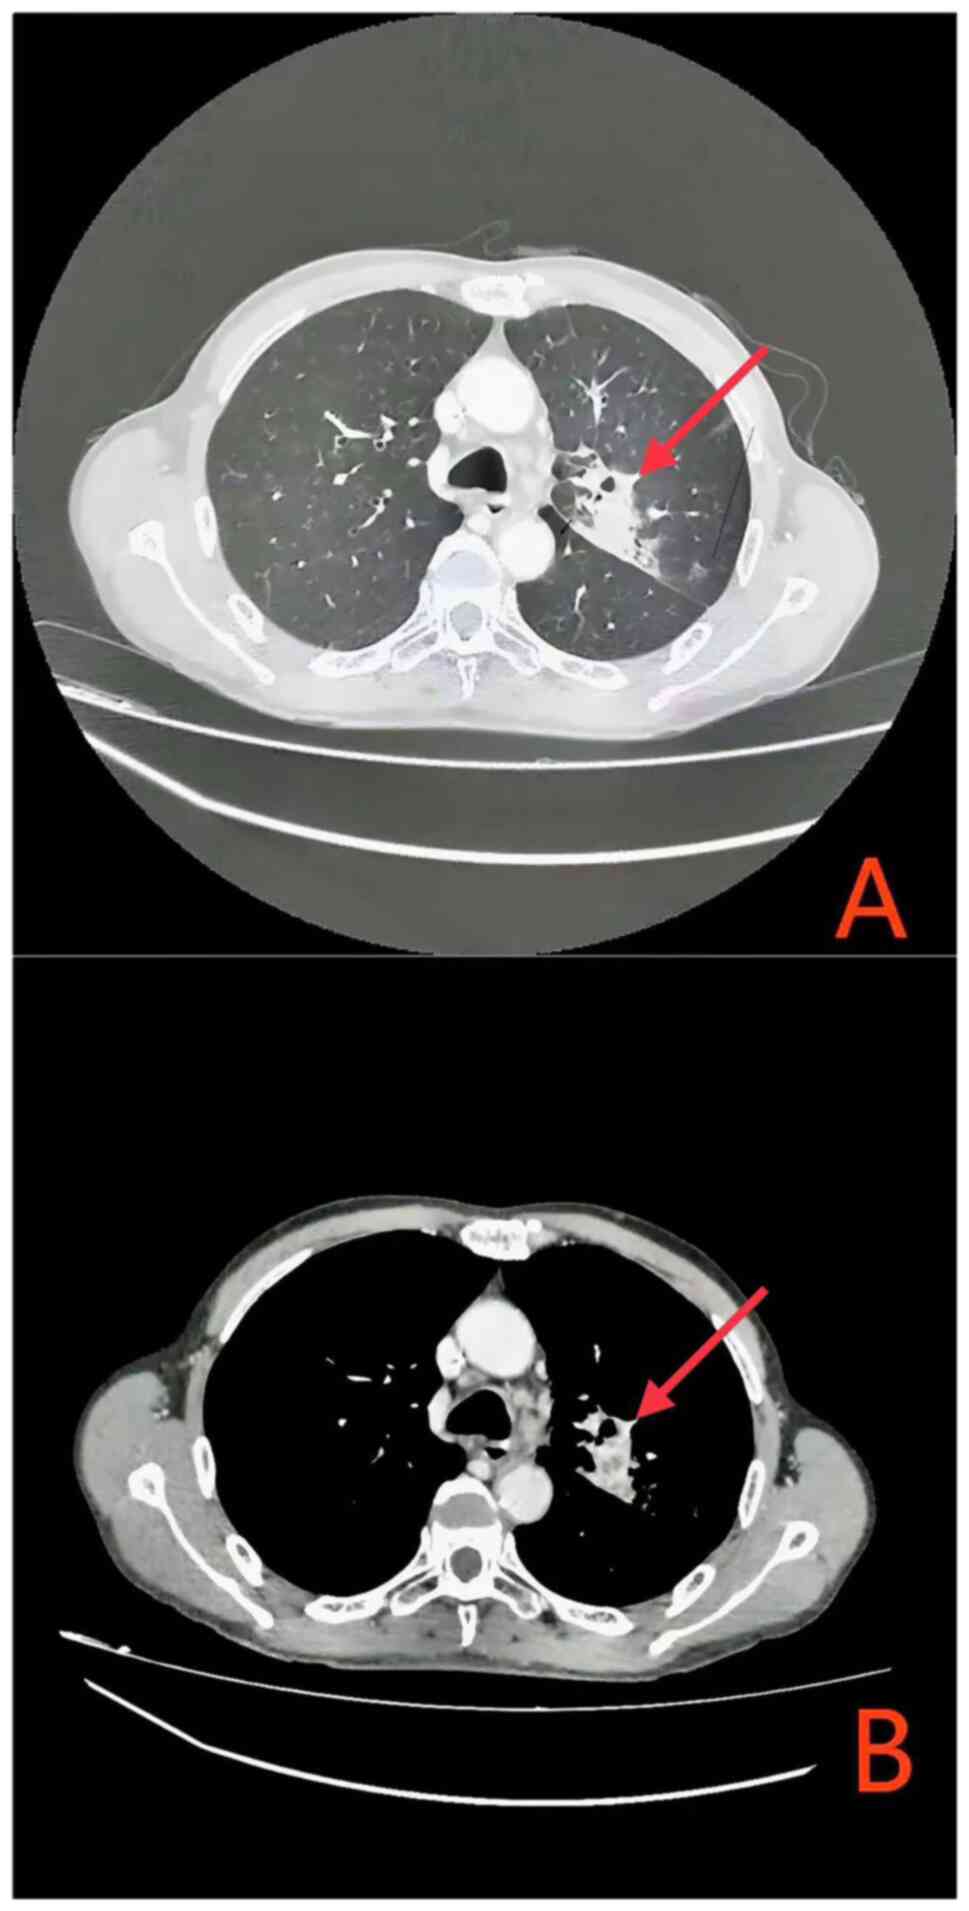

A 61-year-old male patient presented to the Second People's Hospital of Guiyang, (Guiyang City, Guizhou Province, in July 2023, exhibiting a persistent cough accompanied by hemoptysis for a duration exceeding two months. Enhanced chest computed tomography (CT) revealed a suspected left upper lobe lung cancer with obstructive pneumonia (Fig. 1A). Further CT imaging delineated atelectasis in the left upper lobe, the primary lung lesion measuring only 36 mm in diameter, multiple pulmonary nodules indicative of metastatic disease, and enlarged mediastinal lymph nodes (Fig. 1B); however, cranial magnetic resonance imaging, enhanced upper abdominal CT and whole-body bone imaging showed no significant abnormalities. Bronchoscopic pathological biopsy was performed and the pathological analysis of the tissue specimens demonstrated the presence of squamous cell carcinoma of the lung (For routine tissue staining, we utilize Hematoxylin and Eosin (HE) staining. Specifically, tissues are fixed in 10% formalin at room temperature for 6 h, and the slices are cut to a thickness of 3 µm. The staining protocol proceeds as follows: three xylene baths, each lasting 3 min; two baths of absolute ethanol, each for 3 min; a single bath of 95% alcohol for 2 min; two hematoxylin baths, each for 5 min; a brief 3-sec exposure to hydrochloric acid-alcohol; a 1-min treatment with lithium carbonate; eosin staining for 30 sec; and rinsing through a series of alcohol baths with varying concentrations (75% for 10 sec, 85% for 10 sec, 90% for 10 sec, and 95% for 1 min), followed by two baths of absolute ethanol, each lasting 2 min. Microscopic examination is performed using a LEICA2000 microscope. For immunostaining, paraffin-embedded tissues are fixed in 10% formalin at room temperature for 6 h. No resin treatment is employed, and the slice thickness remains at 3 um. No permeabilization reagents are used. Antigen retrieval and exposure for paraffin-embedded tissues are primarily achieved through high pressure and high-temperature treatment with EDTA repair solution, facilitating superior binding of antibodies to their respective antigens. A 3% H2O2 blocking reagent is applied for 15 min at room temperature, and no serum blocking is utilized. The primary antibodies and their respective dilutions, catalog numbers, and suppliers are: CK 1:300, CgA 1:200, Vimentin 1:400, EMA 1:200, Ki-67 1:200, P53 1:200, CK5/6 1:250, P40 1:200, P63 1:200, TTF-1 1:200, Napsin-A 1:150, Desmin 1:100, S-100 1:200, CD56 1:150, Syn 1:200. All antibodies are provided by Wuxi OriGene Biotechnology Co., Ltd. and incubated at 37°C for 1 h. The secondary antibodies are prepared as working solutions, with the catalog number specified as HRP (horseradish peroxidase). The supplier is Venta Medical Group, and the incubation conditions. The secondary antibody is diluted to a working solution, with the catalog number specified as HRP (horseradish peroxidase). The supplier is Venta Medical Group, and the incubation conditions are 37°C for 30 min. DAB is used, with the detection reagent named as DAB Chromogenic Solution. The type of microscope used is a LEICA2000 microscope), devoid of any indicia of small cell components (Fig. 2). This observation unequivocally precluded the possibility of small cell carcinoma in the differential diagnostic considerations. The laboratory evaluation pertaining to liver and kidney functionality, electrolytes and lymphocyte subsets are outlined in Tables I and II. Upon performing a thorough assessment of the driver genes of the patient, no clinically significant genetic mutations were identified. PD-L1 tumor proportion score of the patient was noted to be <1%. The patient was diagnosed with SCC of the left upper lung, obstructive pneumonia and atelectasis, with invasion into the left main bronchus, mediastinum and major blood vessels. Lymph node metastases were confirmed in regions 1R/L, 2R, 3A, 4R/A, 5, 6, 7 and 10R/L, with multiple pulmonary metastases. The disease was staged as cT4N3M1a IVA according to the International Association for the Study of Lung Cancer staging system 9th Edition (8), with PD-L1 expression <1%.

Figure 1.

Before treatment. (Chest contrast-enhanced CT. (A) Adenocarcinoma of the upper lobe of the left lung with atelectasis. (B) Multiple lymph node metastases in the drainage area).